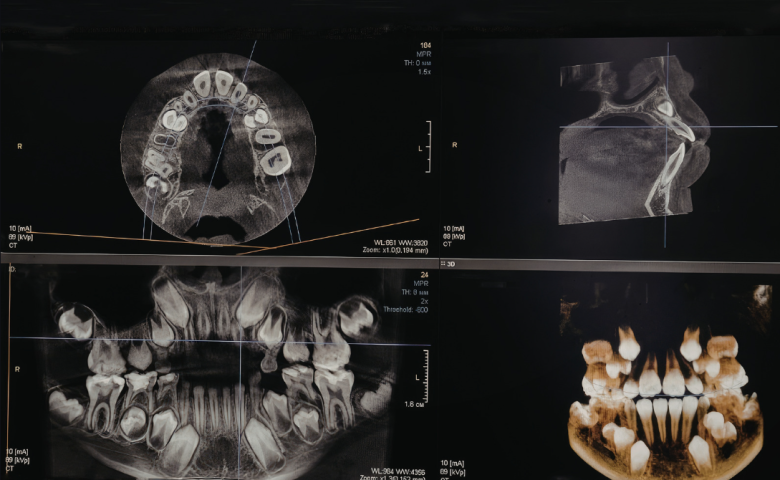

At Shenstone Dental Centre, we believe great dental care starts with using the right technology.

Investing in modern equipment allows us to make treatment more accurate, more comfortable, and often more efficient too. It helps us diagnose problems earlier, plan treatment more precisely, and give our patients a better overall experience from start to finish.

We use advanced dental technology across many areas of the practice, from digital imaging and scanning to treatments for dental implants, Invisalign, hygiene care and cosmetic dentistry. Every piece of equipment we introduce is chosen because it helps us deliver a higher standard of care.